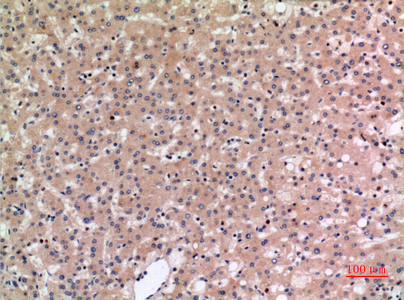

Immunohistochemistry analysis of paraffin-embedded Human liver using SLC10A1 antibody.High-pressure and temperature Sodium Citrate pH 6.0 was used for antigen retrieval.